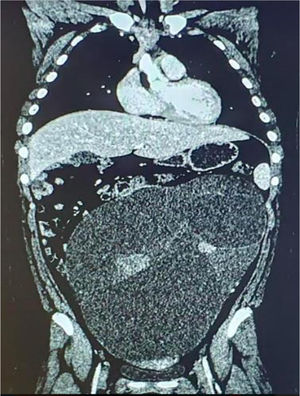

Presentamos una paciente de 13 años con un cistoadenoma mucinoso borderline gigante de ovario. La paciente comenzó con dolor abdominal, náuseas, vómitos y masa palpable. La ecografía y la TAC apuntaban a cistoadenoma vs. cistoadenocarcinoma (fig. 1). Los marcadores tumorales eran normales. Se realizó laparotomía media y salpingooforectomía izquierda, que reveló una neoformación quística multilocular de consistencia irregular y contenido mucinoso de 7kg (figs. 2 y 3). Microscópicamente, se observan varios focos sólidos de células atípicas compatibles con cistoadenoma mucinoso borderline, puesto que cumple el criterio de estratificación nuclear en 2 o 3 capas sin invasión estromal3. Destacamos la importancia del estudio anatomopatológico para realizar un diagnóstico definitivo, pues permite diferenciar los casos benignos, borderline o malignos. El examen citológico fue negativo y la evolución postoperatoria favorable, sin precisar tratamiento adyuvante.